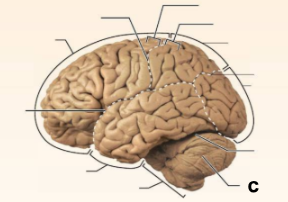

Identify the structure labeled “a” in the image.

Brain Stem

Identify the structure labeled “b” in the image.

Central culcus

Identify the structure labeled “c” in the image.

Cerebellum

Identify the structure labeled “d” in the image.

Frontal lobe

Identify the structure labeled “e” in the image.

Lateral sulcus

Identify the structure labeled “f” in the image.

Occipital lobe

Identify the structure labeled “g” in the image.

Parietal lobe

Identify the structure labeled “h” in the image.

Parieto-occipital sulcus

Identify the structure labeled “i” in the image.

Postcentral gyrus

Identify the structure labeled “j” in the image.

Precentral gyrus

Identify the structure labeled “k” in the image.

Temporal lobe

Identify the structure labeled “l” in the image.

Transverse cerebral fissure